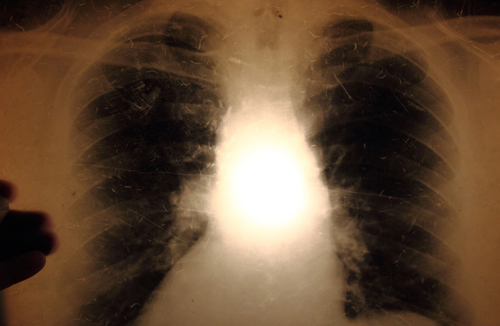

Chest X-rays for tuberculosis (TB) during pregnancy

Chest X-ray examinations for pregnant women are safe with regards to potential harm to the foetus from radiation. The Norwegian Institute of Public Health recommends that chest X-rays are performed on pregnant women as part of the tuberculosis screening to see whether they have pulmonary tuberculosis. If the pregnant woman prefers not to do this, and there is no suspicion of pulmonary tuberculosis, IGRA is an alternative.

X-ray examinations of the lungs of pregnant women are safe with regards to the potential risk of foetal harm from radiation. The International Commission on Radiological Protection (ICRP) estimates that the threshold dose for radiation-induced foetal damage begins at approximately 100 mGy [2,3]. A typical dose to the foetus / embryo during a chest X-ray is less than 0.01 mGy, which is less than 0.01 % (or 1/10 000 part) of the threshold dose for radiation-induced injury. The Norwegian Radiation Protection Authority considers that chest X-rays of pregnant women are safe as long as the examination is justified [4]. The Norwegian guidelines are in line with guidelines from the USA [5].